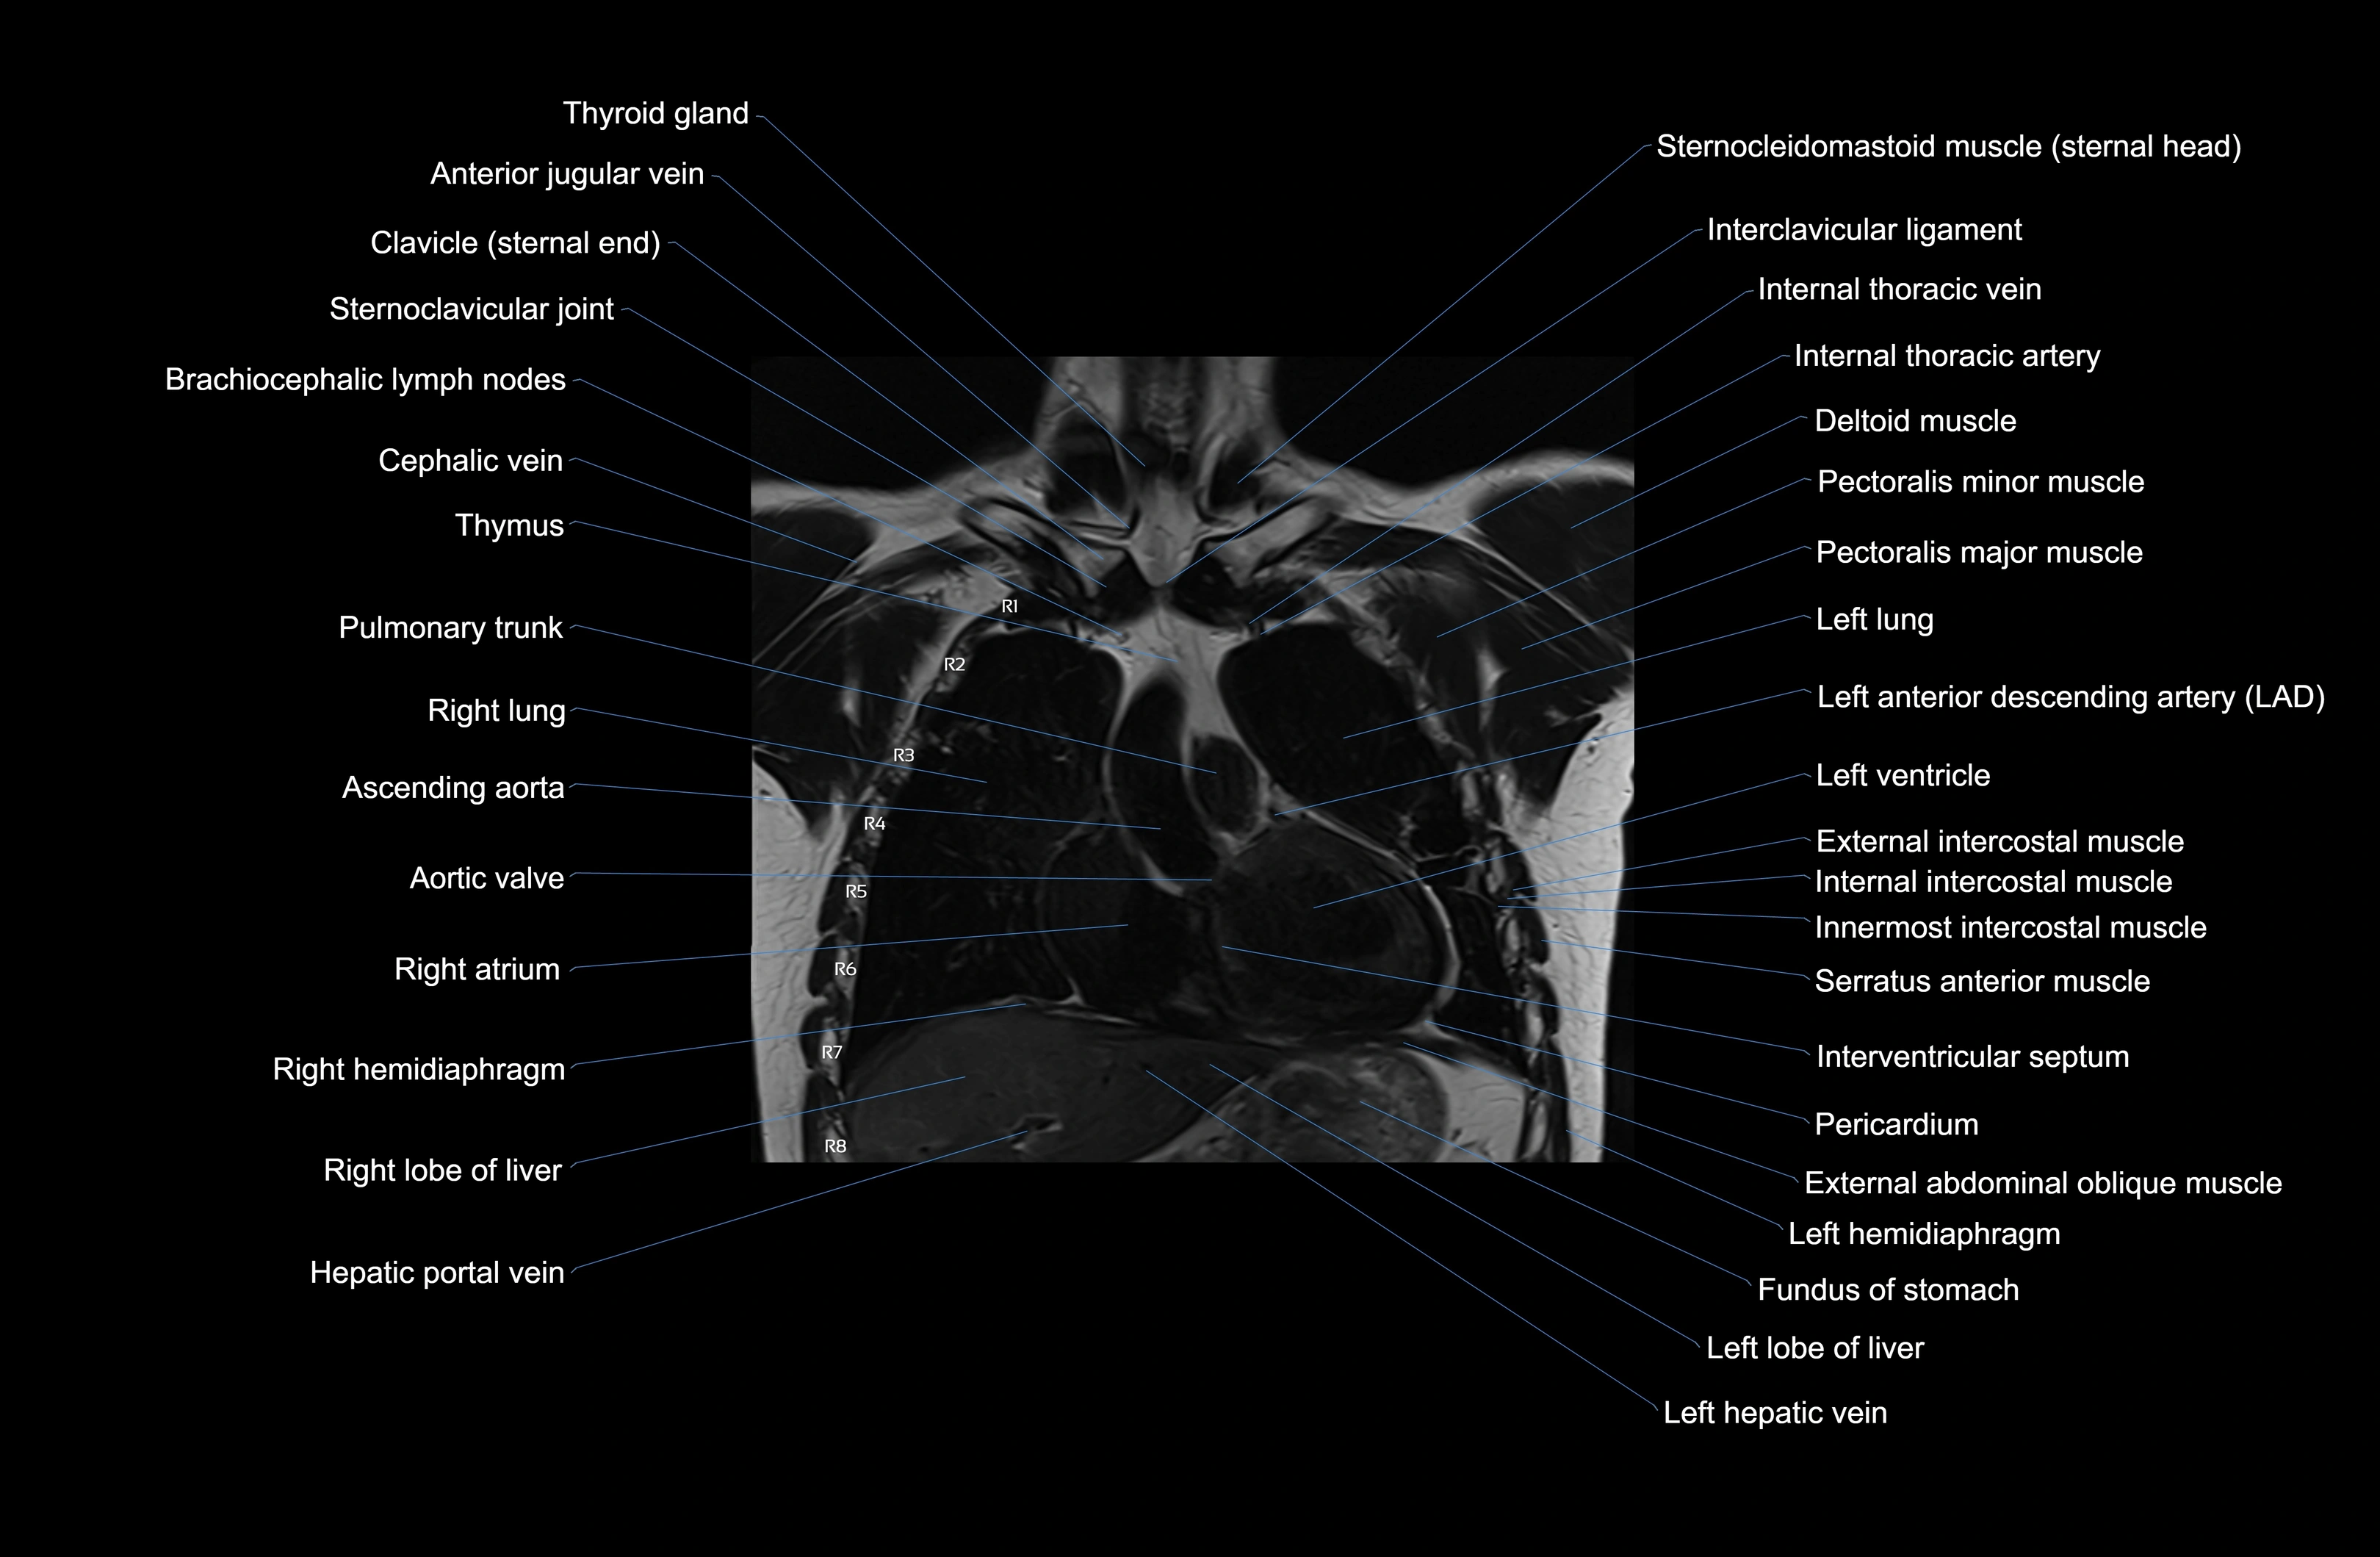

MRI images